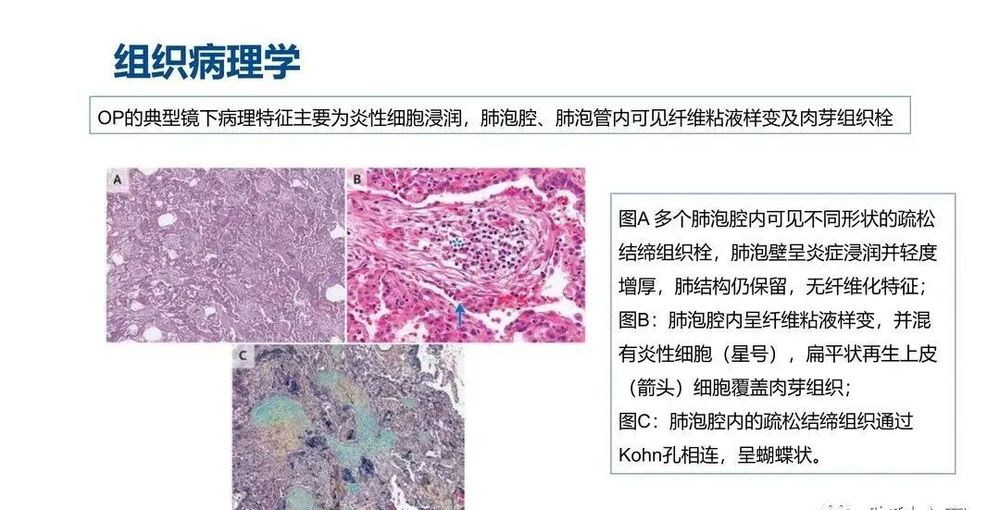

组织病理学

COP患者肺活检标本的组织病理学结果显示腔内有疏松结缔组织栓子,累及肺泡腔和肺泡管,也可累及细支气管,肺的基础结构保留。腔内疏松结缔组织栓子常以细柄连接到肺泡壁,并通过肺泡孔从一个肺泡延伸到相邻的肺泡,形成特征性的蝴蝶状结构。肺泡壁可出现轻度慢性炎症(如涉及淋巴细胞和浆细胞)。

观察到以下情况时,提示有其他诊断:显著的间质慢性炎症(涉及中性粒细胞或嗜酸性粒细胞)、形态不良的肉芽肿、细支气管周围化生、淋巴样聚集、血管炎、间质纤维化或镜下蜂窝状改变。

COP的主要病理变化是肺泡内、肺泡管、呼吸性细支气管及终末细支气管内有息肉状肉芽组织增生,形成Masson小体,其病变表现单一,时相一致,呈斑片状和支气管周围分布,位于气腔内,含极少炎性细胞,肺结构往往正常。肺泡腔内肉芽组织呈芽生状,由疏松的结缔组织将成纤维细胞包埋而构成,可通过肺泡孔从一个肺泡扩展到邻近的肺泡,形成典型的“蝴蝶影”。肉芽组织中可存在炎性细胞,尤其在疾病早期,可见单核细胞、巨噬细胞及少量的肥大细胞、嗜酸粒细胞、中性粒细胞。在空的肺泡腔内可见肺泡巨噬细胞,部分肺泡巨噬细胞呈泡沫状,伴有Ⅱ型肺泡上皮细胞增生。受累的肺泡间隔有少量淋巴细胞和浆细胞浸润为主的轻度炎性渗出,肺泡间隔稍增厚。